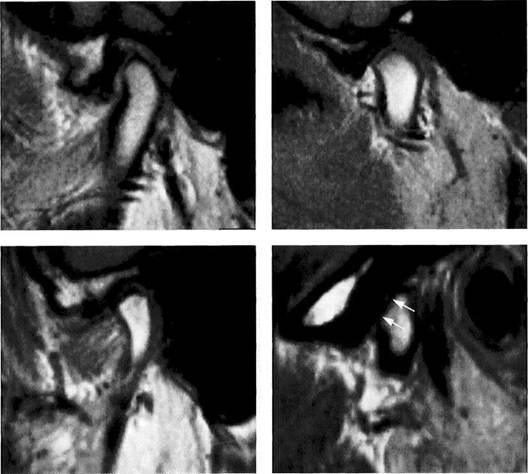

Disk position in the frontal plane

Physiological disk position

Left: Schematic drawing illustrating normal disk position in the frontal plane.

Right: MRI of the right temporo­mandibular joint of a 24-year-old man. The frontal plane is angled so that it is parallel with the long axis of the condyle. With the jaws closed, the pars posterior of the disk is centered over the condyle.

Medial disk displacement

Left: Schematic drawing of a medial disk displacement in the frontal plane.

Right: MRI of the right temporo­mandibular joint of a 24-year-old patient. An adequate diagnosis of lateral and medial disk displace­ments cannot be made with arthrography and arthrotomogra-phy alone (Kurita et al. 1992a,b).

Lateral disk displacement

Left: Schematic drawing of a lateral disk displacement in the frontal plane.

Right: MRI of the right temporo­mandibular joint of a 23-year-old woman who sustained a fracture of the neck of the condyle at age 14 years. The condyle was tipped medially and has healed in an ab­normal position. The lateral disk displacement is causing pain and recurring limitation of jaw opening.